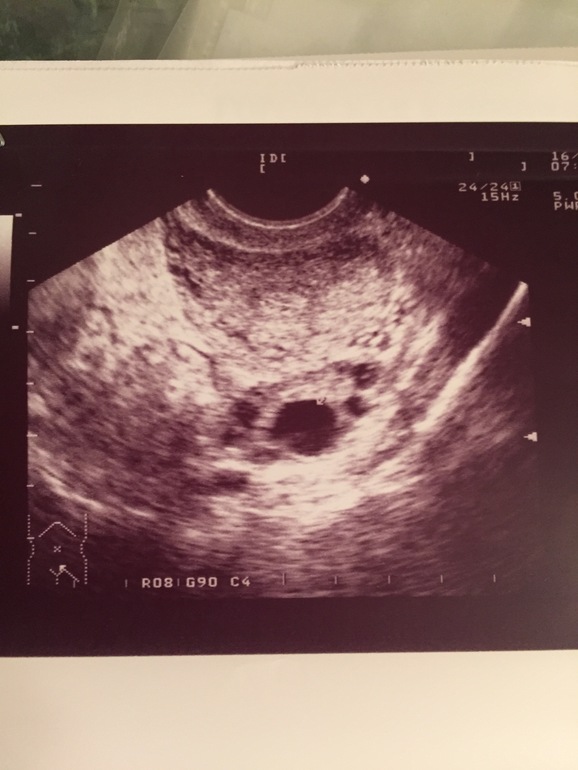

Была на интравагинальном узи на 8дц, врач увидела дф 15х12мм..договорились, что приду на 14 дц посмотреть динамику и отследить О..вообщем сделали узи, и врач сказала, что она видит все тот же дф, размеры его 14х13, никакое это не жт, и это очень странно, что он никак в размерах не изменился и О конечно не было...по моим ощущениям и цж, О у меня была на 13 дц, но узистка, очень опытная, с многолетним стаже, с уверенностью отрицает..я в полном недоумении..остальные показатели у меня как положено для второй стадии..она меня очень расстроила..девочки, напишите Ваше мнение пожалуйста по -поводу снимков узи..8дц

Второй снимок точно ЖТ - моя узистка так м говорит - видишь образование похожее на звездочку, знай - ЖТ.

Я бы сказала так, на первом выглядит как дф, на втором как жт. Странно